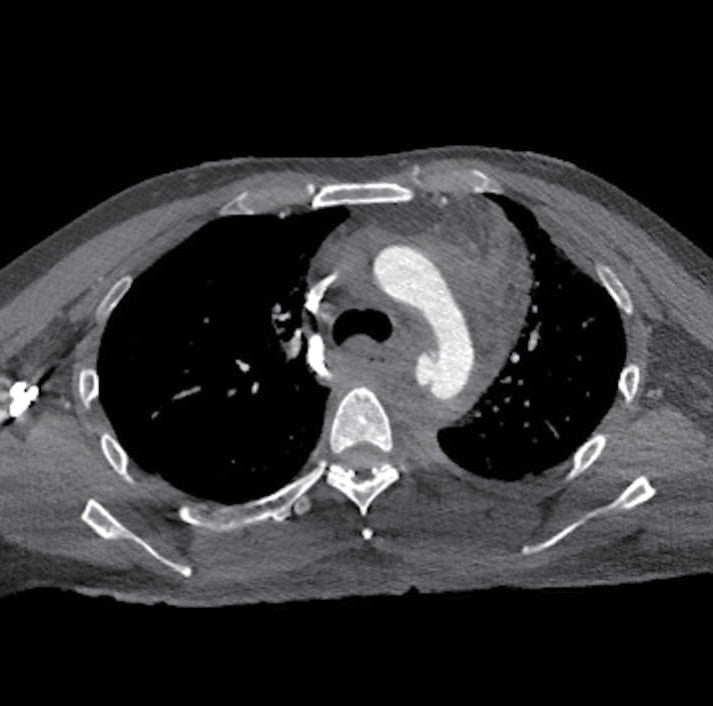

症例は45歳男性で列車事故のため受傷し救出されたが、意識は清明であるものの血圧60台のショック状態で、現場から救急搬送された。当院での造影CTでは近位下行大動脈損傷による破裂と周囲の縦隔血腫を認めた。他には恥坐骨と手の骨折を認めるのみで、頭部、腹部に外傷を認めなかった。緊急輸血を行いつつステントグラフトによる治療を行う方針となった。

術前のサイジングで中枢ランディング径は25 mmであり、左鎖骨下動脈から大動脈損傷部までのランディング長は小弯側の測定で18 mmであった。外傷により損傷されている部位の長軸方向の長さは40 mm程度であるが、その遠位の下行大動脈は壁内血腫様の所見であった。遠位ランディング径は21-23 mmであり、ステントグラフトは28 mm-15 cmを使用することとした。